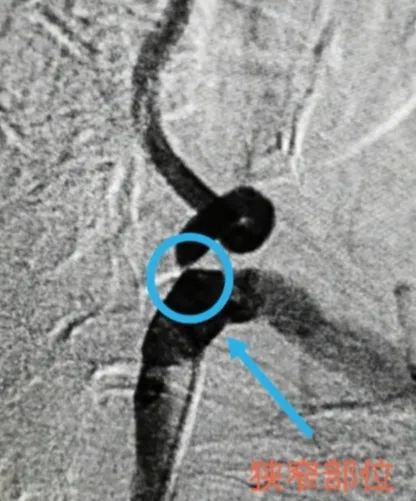

术前↓:造影显示椎动脉狭窄部位

2019年,那时还在*疆新**生活的齐大爷出现了头晕、头痛,但因昏痛症状每次都能自行缓解所以也并未在意,直到后来还出现了心悸、恶心,齐大爷才决定去医院检查。在当地医院,齐大爷被诊断为脑动脉供血不足、腔隙性脑梗死、高血压三级,虽然治疗后有所好转,但没过多久,头晕、头痛的情况又发生了!2020年,齐大爷再度求医,在当地医院经过颈部CTA检查后显示,他的右侧椎动脉闭塞,左侧椎动脉起始端狭窄。原来,这就是造成齐大爷反复头晕头痛的罪魁祸首。

据神经外科主任冉义生介绍,椎动脉狭窄可在颅外或颅内任何部位发生。人体有左右两根椎动脉,主要负责脑组织后循环供血。一旦椎动脉出现问题,可能引发脑梗,出现神经功能障碍时还将危急生命。

这种病症的主要原因是由椎动脉狭窄引起,为此,在治疗上必须对症下药才能解决齐大爷的顽疾。综合考虑到患者年龄、身体状况、恢复情况和治疗效果等方面,科室团队为齐大爷制定了详细的治疗方案,决定采取 微创手术治疗——椎动脉狭窄球囊扩张支架植入术 。